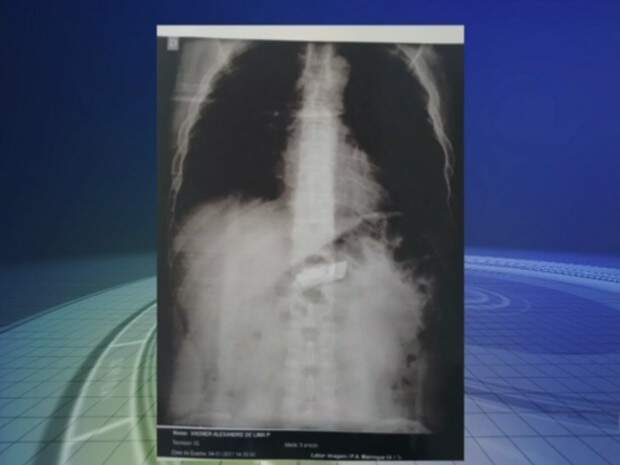

Detento é operado para retirada de celular do estômago